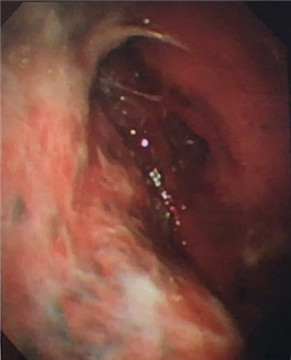

7月21日建立人工氣胸,擴(kuò)張肺部。7月22日,由周傳毅主任、張健主治醫(yī)師共同實(shí)施了胸腔鏡檢查,并活檢取出多處胸膜小結(jié)節(jié)。術(shù)后經(jīng)病理診斷,確診為結(jié)核性胸膜炎。檢查過(guò)程無(wú)任何不適,后續(xù)配合抗結(jié)核藥物治療,王爺爺恢復(fù)良好,已出院返家。

多發(fā)黃白色小結(jié)節(jié)

我院呼吸內(nèi)科采用改良型“軟式胸腔鏡”,該新設(shè)備軟硬結(jié)合,前端可彎曲,能多方向觀察胸腔內(nèi)改變,比老式“硬式胸腔鏡”的探查視野更大,診斷更準(zhǔn)確。